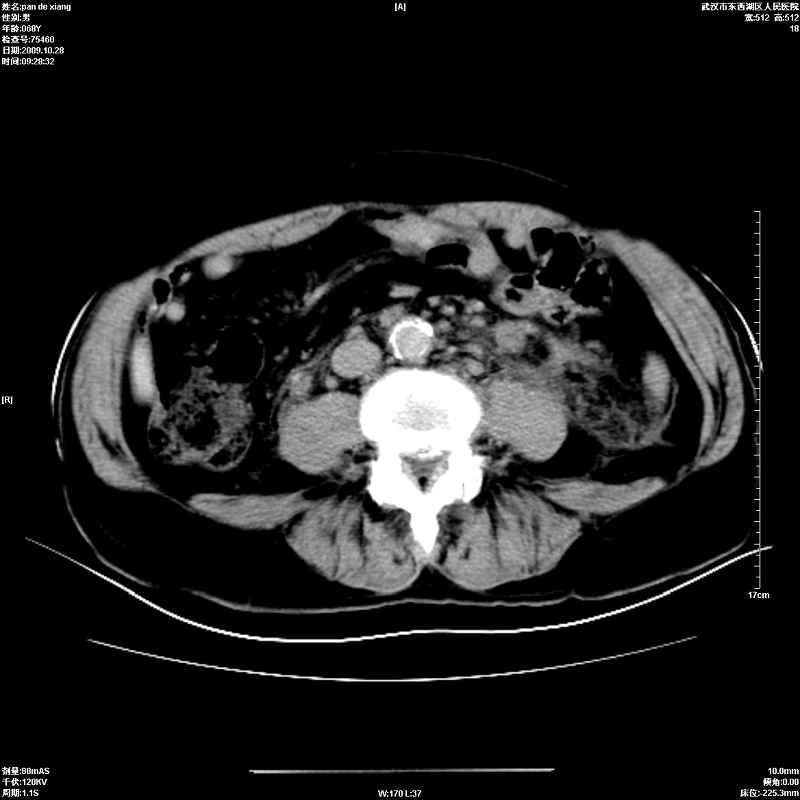

以下是引用杀毒软件在2009-10-28 20:41:00的发言:[br]结合临床考虑---白血病双肾改变或淋巴瘤。

以下是引用zxl51642在2009-10-29 9:59:00的发言:[br]结合临床“单克隆免疫球蛋白血症”,考虑双肾为继发损害并肾功能不全(尿中大量igg及少量iga、igm等大分子免疫球蛋白滤出所致继发损害),椎前软组织肿块为髓外造血。与浆细胞瘤有区别,平扫时有战友说的很清楚。